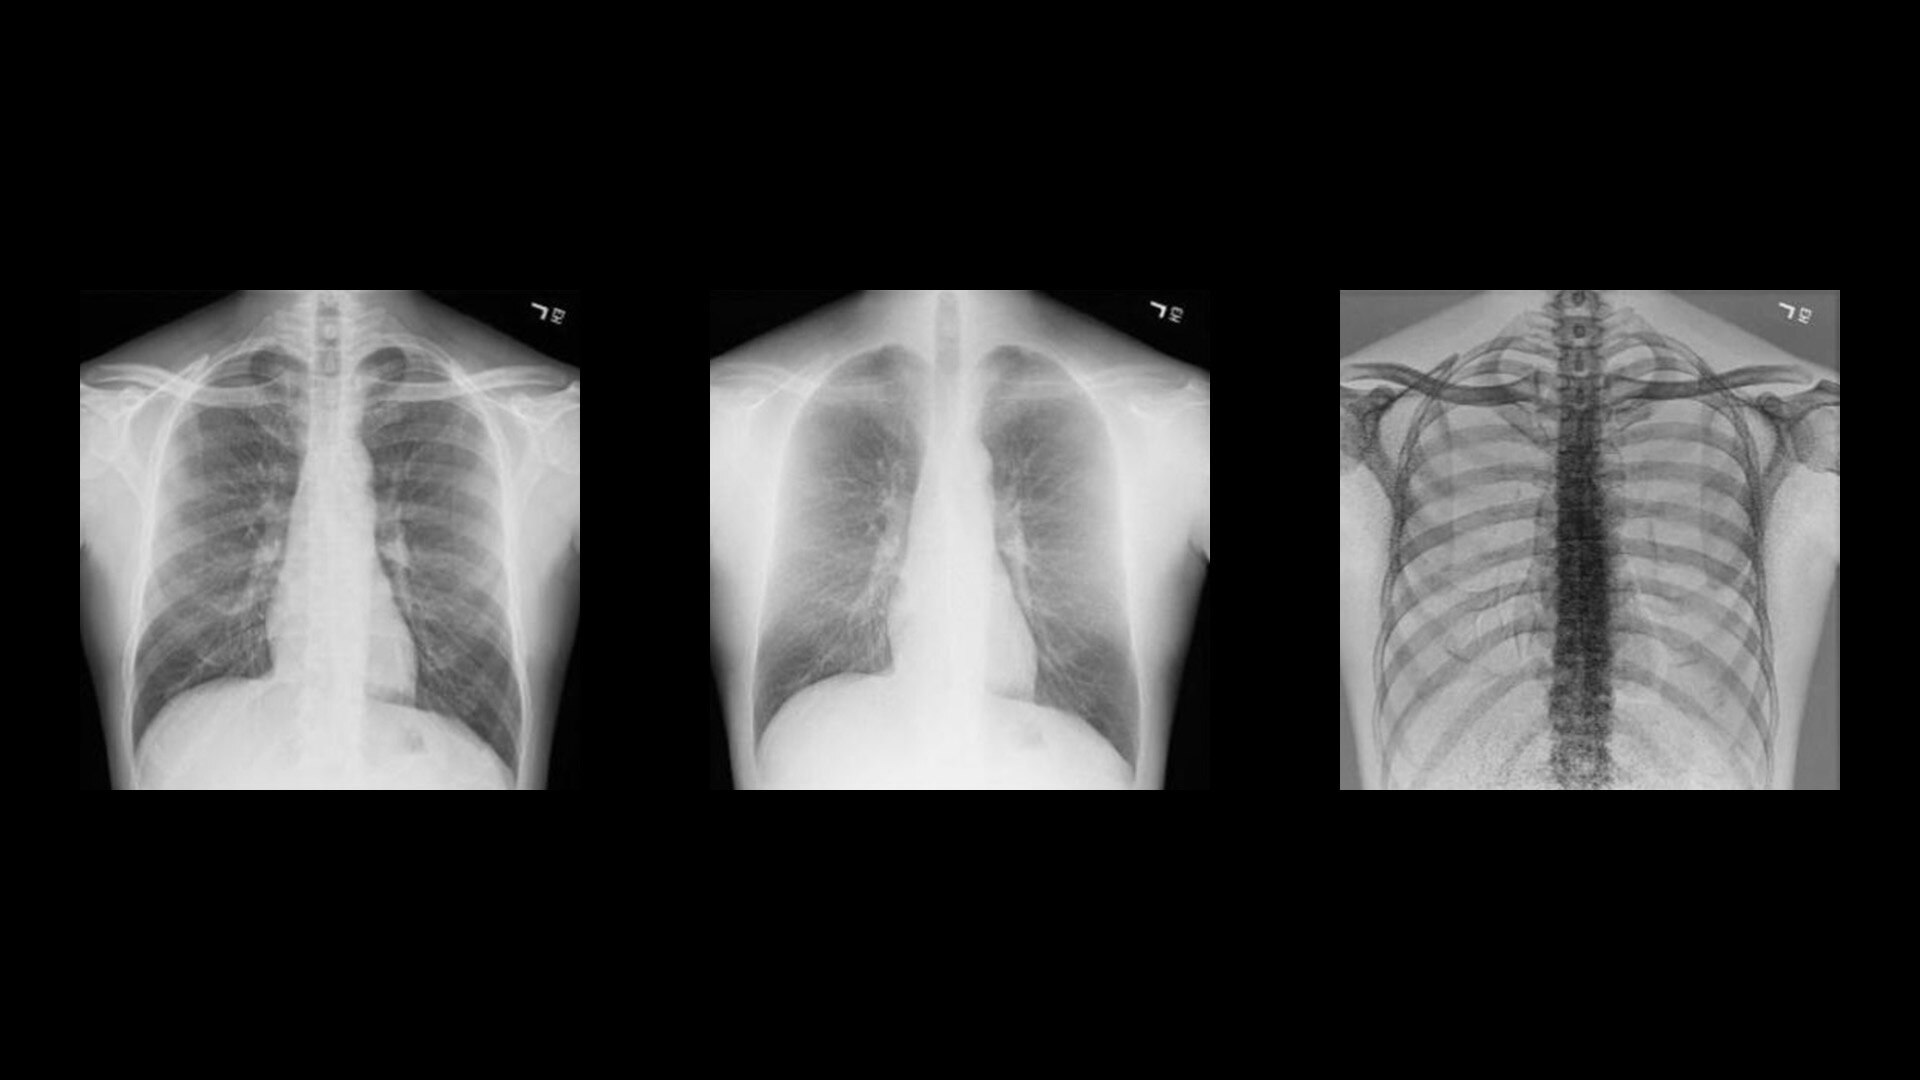

Two acquisitions. Three images.

Rather than relying solely on algorithmic image processing, Dual Energy Subtraction acquires two exposures at different energy levels in less than 160 milliseconds. You can process and view the image as:

• A standard radiographic image

• An image with bones subtracted

• An image of just the bones to highlight foreign objects or calcified structures

These images help you detect abnormalities that may have been obscured in a conventional radiograph.